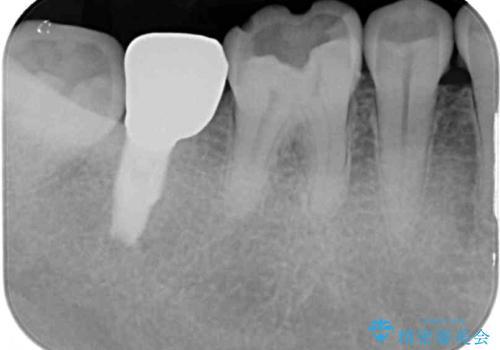

- 奥歯に装着されていたゴールドインレーが外れてしまったとのことで来院された患者様です。

外れてしまったインレーをはめたところ、インレー周辺の歯質が虫歯で失われていました。

虫歯をしっかりと取り除き、改めてゴールドインレー(PGAインレー)にて修復することとしました。